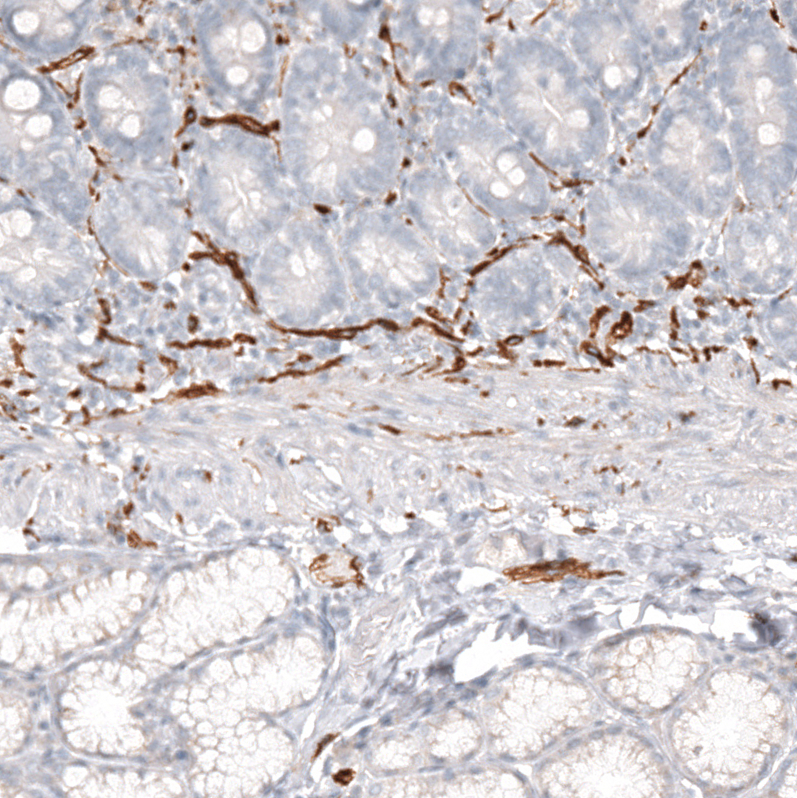

Immunohistochemistry analysis in human cerebral cortex and skeletal muscle tissues using AMAb91807 antibody. Corresponding NCAM1 RNA-seq data are presented for the same tissues.